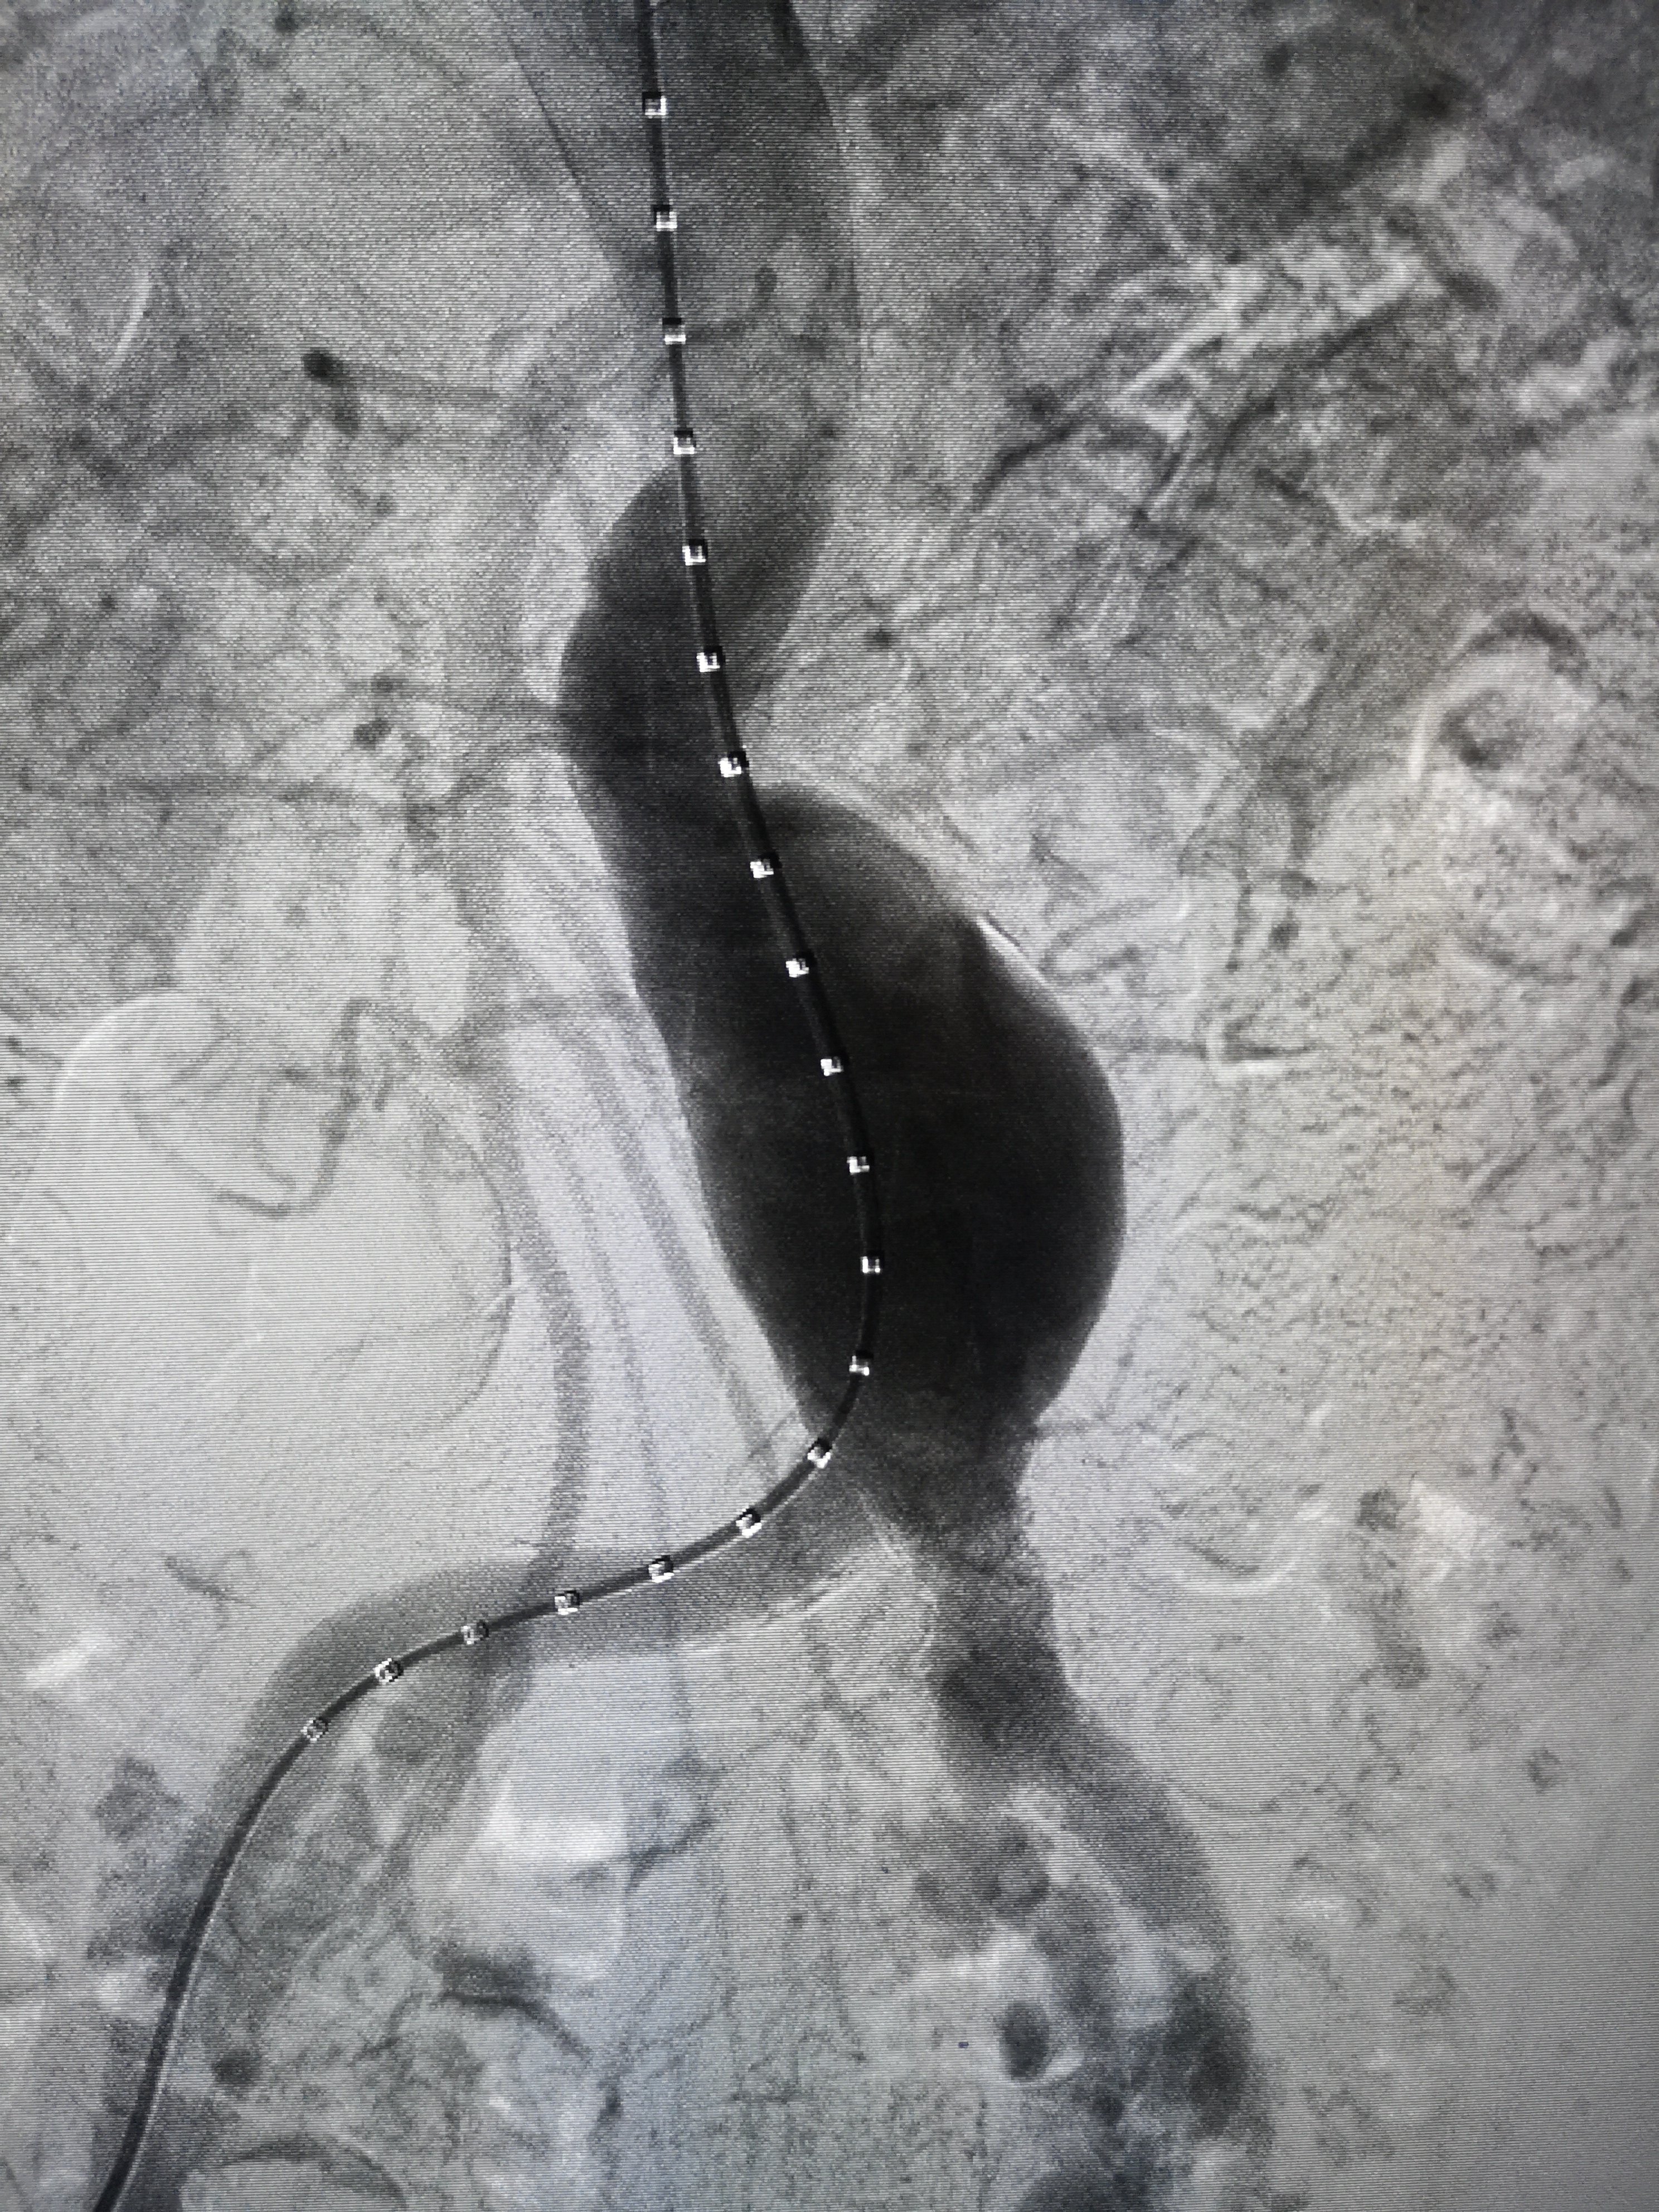

主动脉造影可见动脉瘤瘤样扩张,体内不定时炸弹支架植入隔绝主动脉瘤

腹主动脉覆膜支架腔内隔绝术